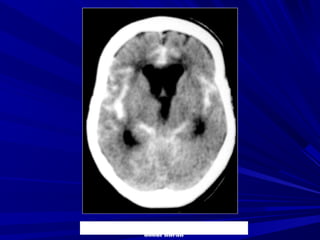

Giai ñoaïn toái caáp (< 6 giôø)

- Bình thöôøng (50-60%)

- Daáu taêng ñaäm ñoä ñoäng maïch 25-50 %

- Giaûm ñaäm ñoä nhaân ñaäu

HÌNH AÛNH CT ÑOÄT QUÎ

TMNCBC